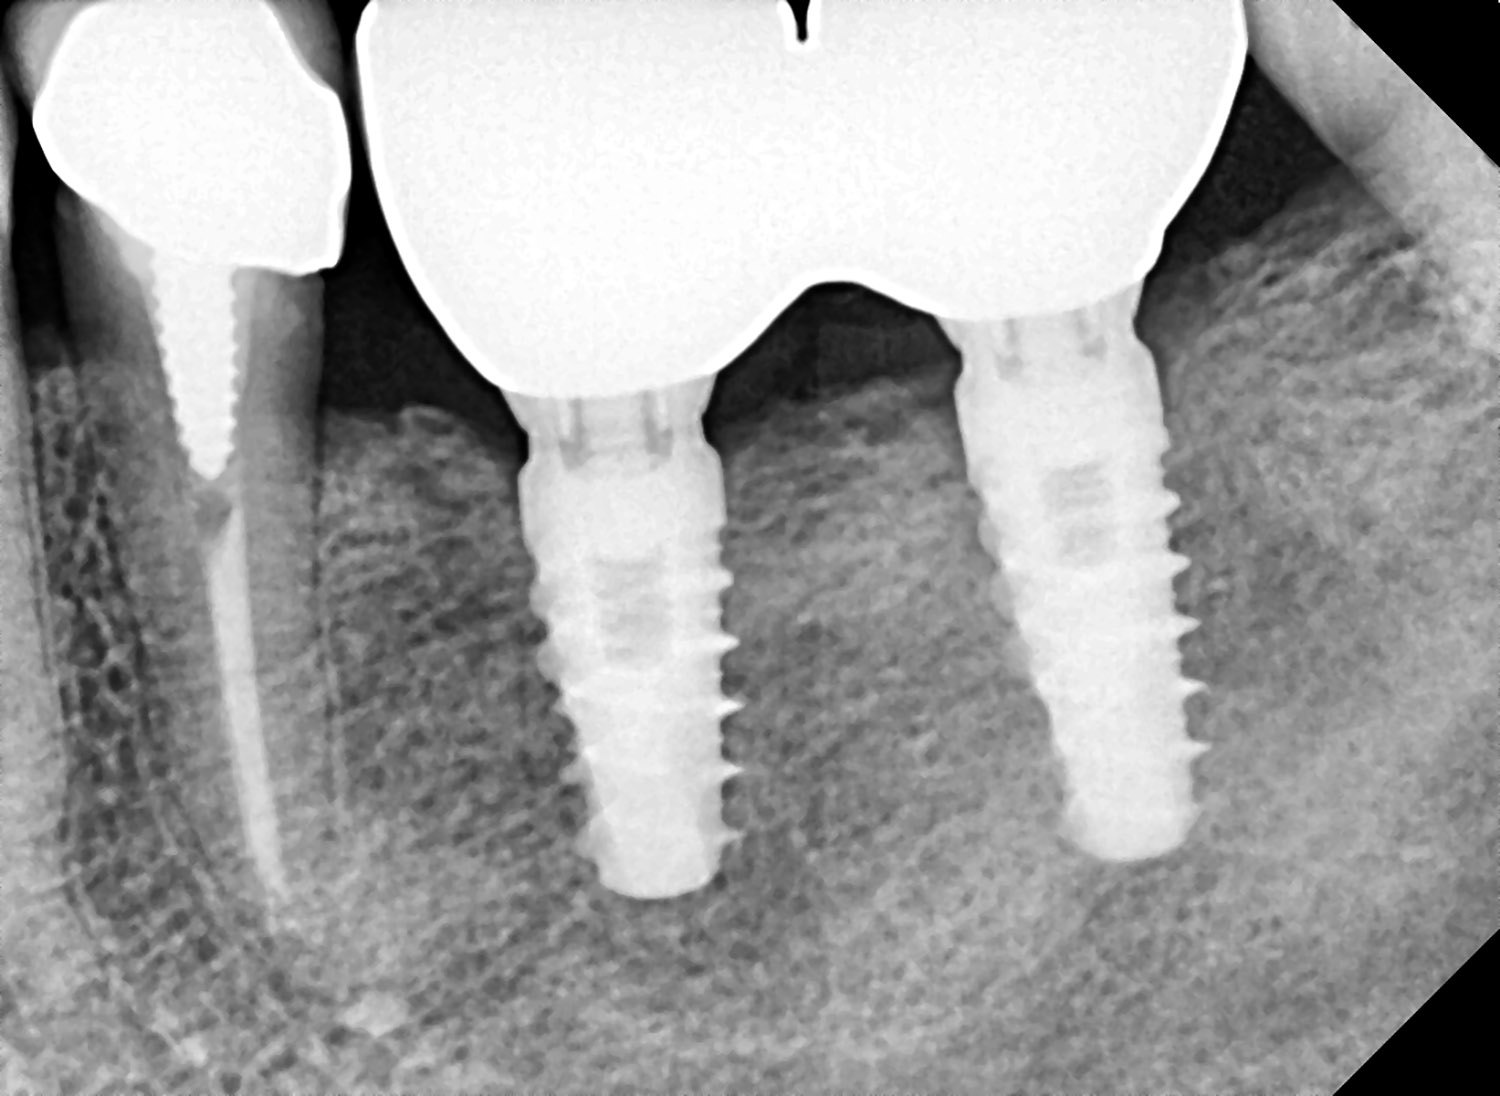

Esistono varie soluzioni per sostituire uno o più denti mancanti; tra queste, una è rappresentata dagli impianti. L’impianto è una struttura in titanio, normalmente di forma simile a quella di una radice dentaria, che viene inserita, con un intervento in anestesia locale, nella mandibola o nel mascellare superiore e che è in grado di sostituire funzionalmente ed esteticamente il dente o i denti mancanti.

Una volta inserito l’impianto, prende avvio un processo di guarigione che porta alla sua integrazione nell’osso (osteointegrazione). In base alle indicazioni e al quadro clinico è possibile inserire uno o più impianti creando, quindi, le premesse per l’applicazione di una corona singola o di un manufatto protesico, più o meno esteso.